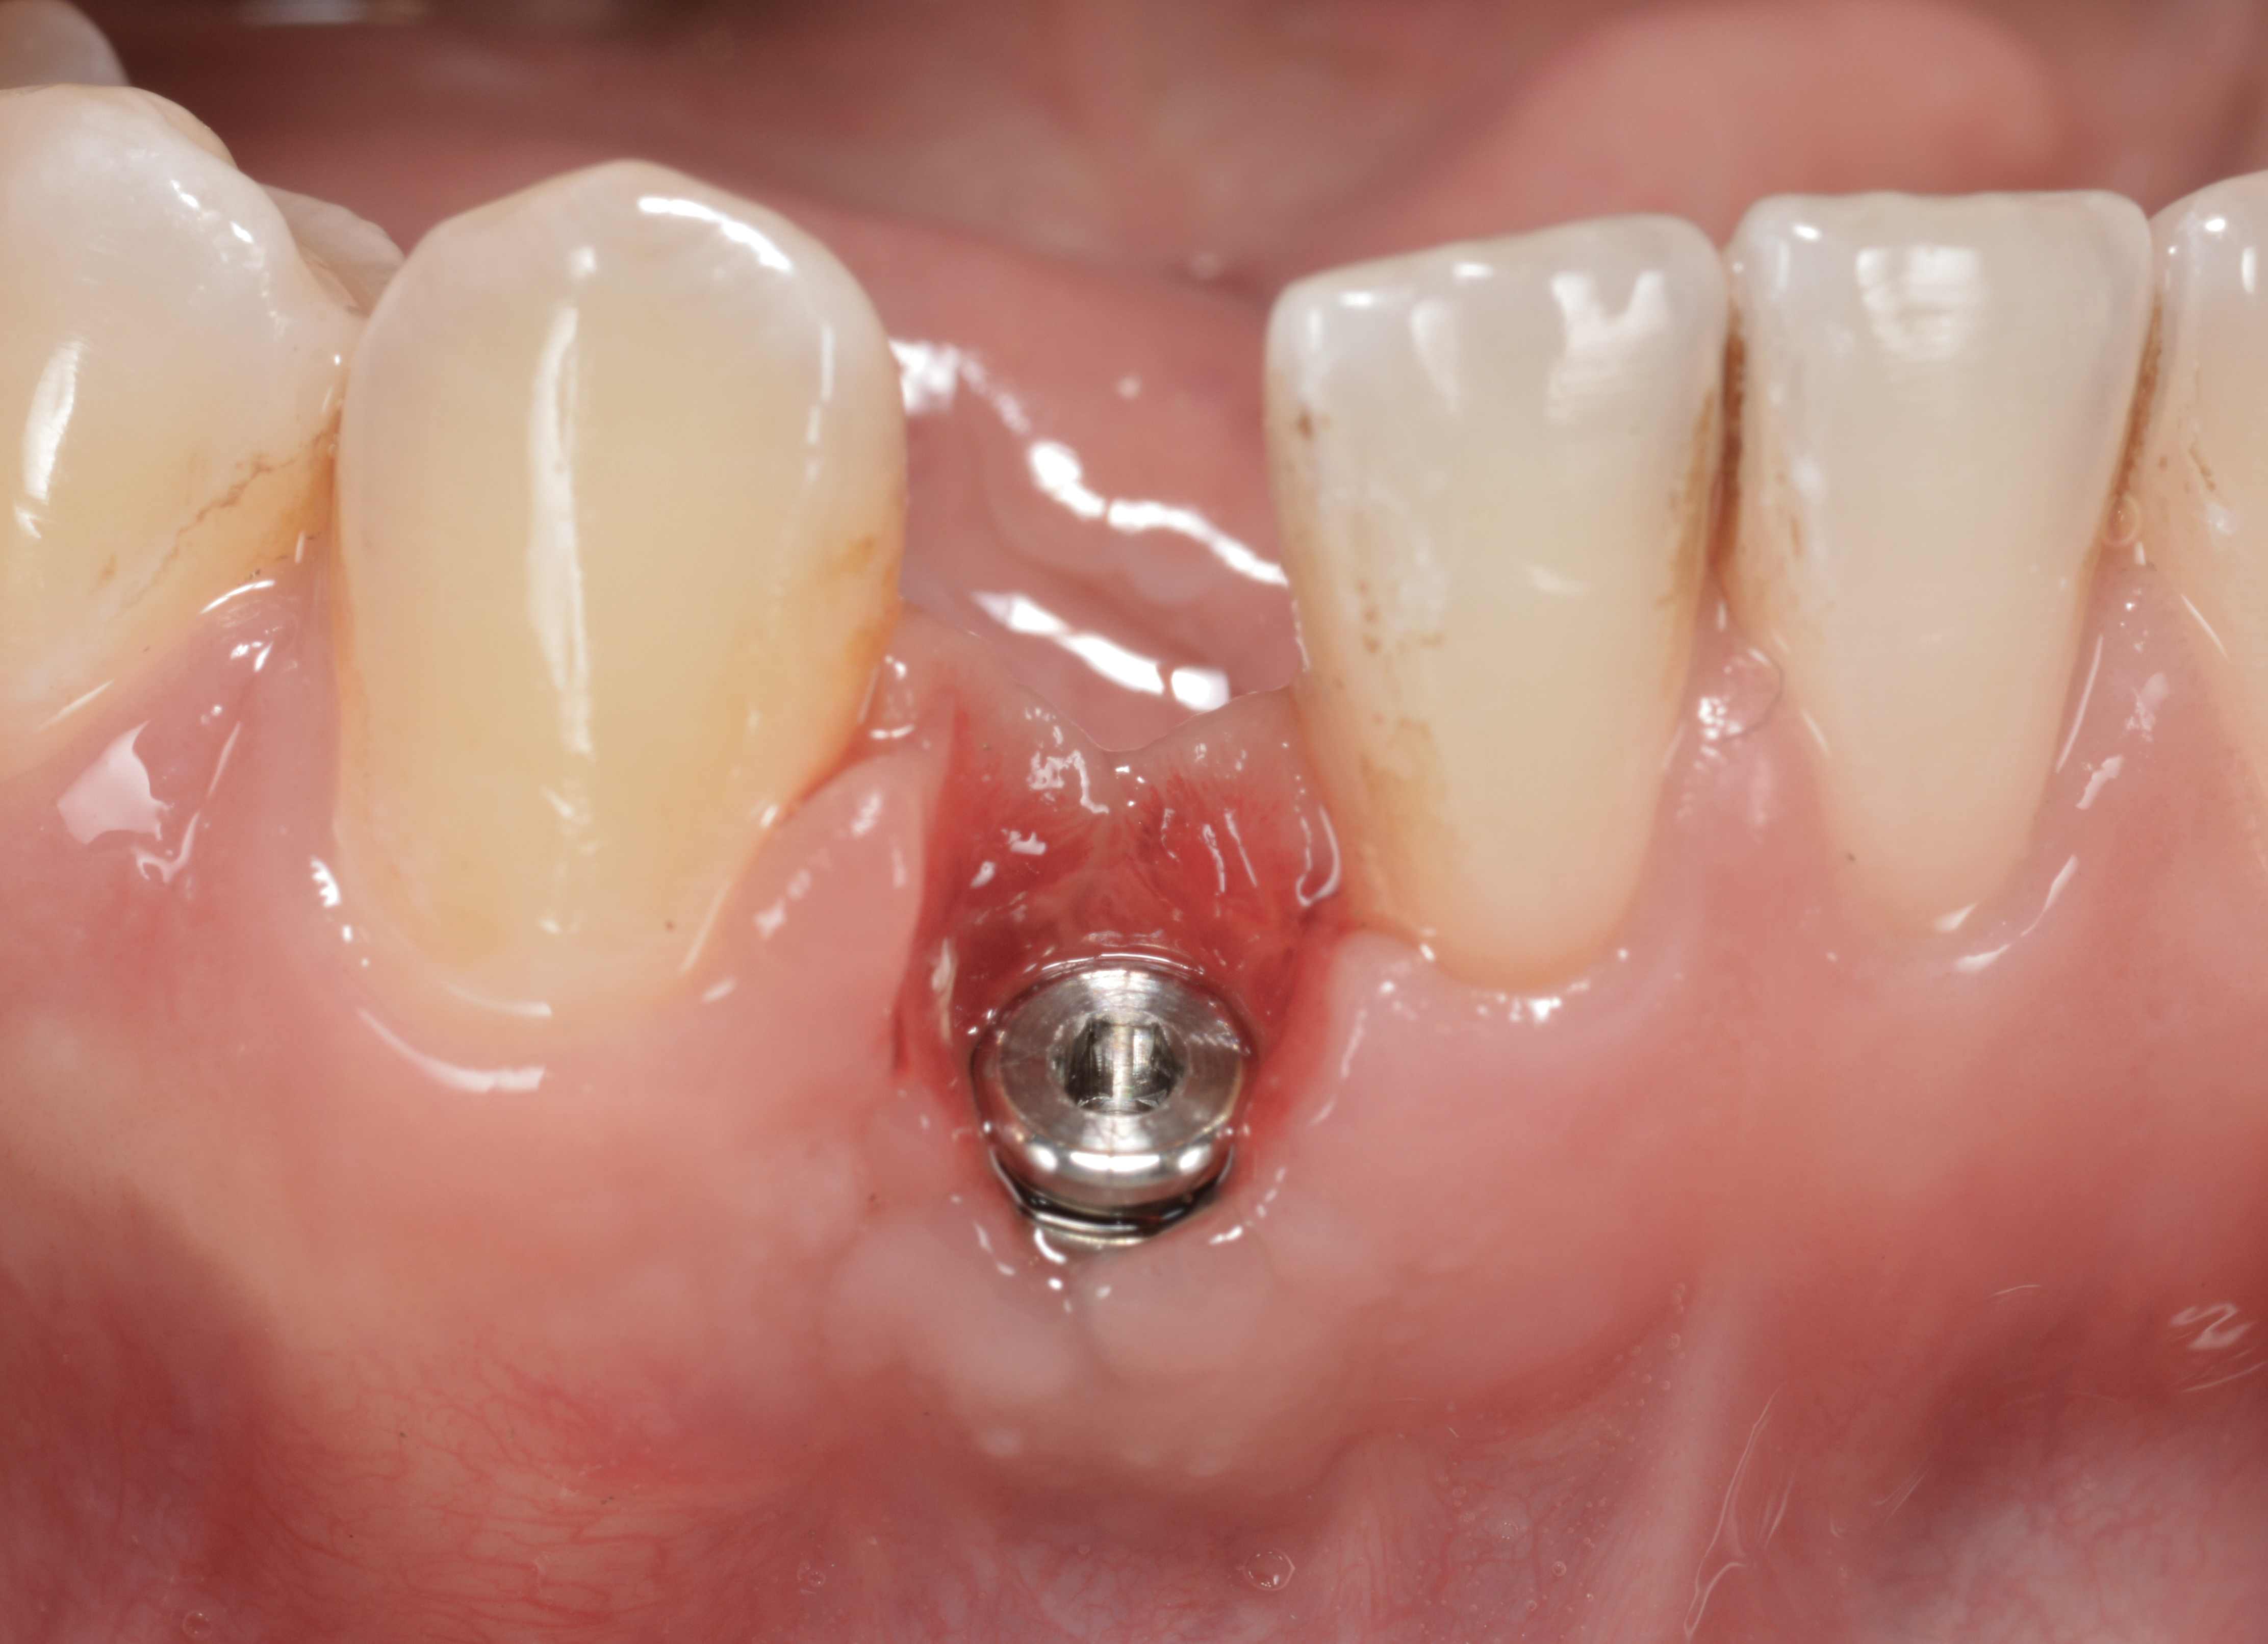

Fig 33. Excessive facial angulation of the implant placement shown with an abutment driver in the access screw hole.

Figure 33

Fig 34. A surgical cover screw was placed in an attempt to decoronate the implant and gain soft-tissue coverage in situ.

Figure 34

The following case report provides an example of this case scenario: A 24-year-old white male presented with congenitally missing tooth No. 26 restored with a single-tooth cement-retained implant restoration. The implant was placed excessively to the facial aspect of the edentulous site and too shallow, and the periodontal phenotype was thin scalloped (Figure 32). In an effort to mimic the lost midfacial soft tissues, pink ceramics were used as a cosmetic facade. Even though the restoration was not in the esthetic zone, the patient was highly displeased with the esthetic outcome and sought remediation.

The crown and screw-retained custom abutment were removed, and a surgical cover screw was placed into the implant, thereby allowing spontaneous gingival augmentation in situ (Figure 33 and Figure 34). Note that the lingual aspect of the implant site was significantly more coronal than the labial aspect, which was positive because the defect would be limited to a facial–lingual defect. A fixed RBR bridge was cemented on the adjacent teeth and used as a tooth-supported transitional provisional restoration (Figure 35). A few weeks were allotted to let the soft tissue heal and migrate around the cover screw (Figure 36) to see if there would be complete coverage, thereby allowing a soft-tissue augmentation procedure to be performed with primary flap closure as in clinical scenario No. 2. The major obstacle in achieving a positive tissue response was that the implant depth was also deficient because the implant–abutment connection was at the level of the free gingival margin. It was decided that the best treatment option would be to remove the implant. A high-powered reverse-torque device (Fixture Remover Kit, NeoBiotech, www.neobiotechus.com) was used to remove the implant atraumatically (Figure 38 through Figure 41). The implant socket was allowed to heal for several months not unlike an extracted tooth (Figure 42). A new implant was placed in a better position from both a restorative and esthetic perspective (Figure 43), and after a few months of healing, a new crown was made (Figure 44). A satisfactory functional and esthetic result was achieved (Figure 45 and Figure 46) without employing pink porcelain.